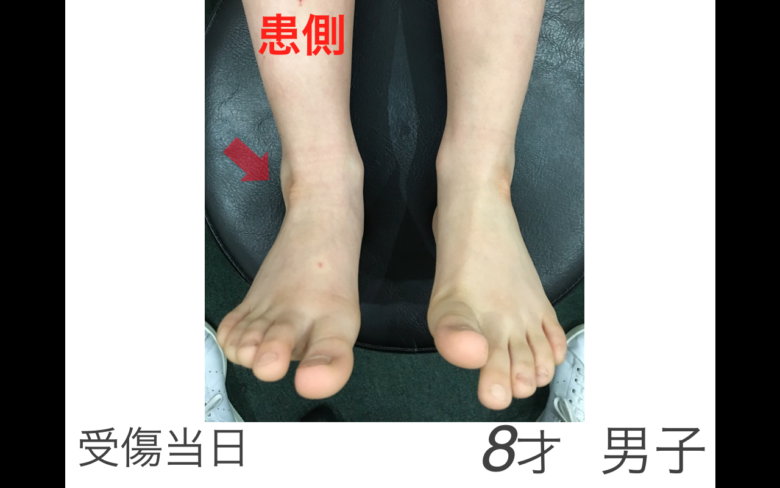

子供さんの足首の骨折

子供さんの足首の骨折

子供さんの足首の骨折

腓骨遠位骨端線損傷 小児の骨折と成人の骨折ではどう違うの 古東整形外科 リウマチ科